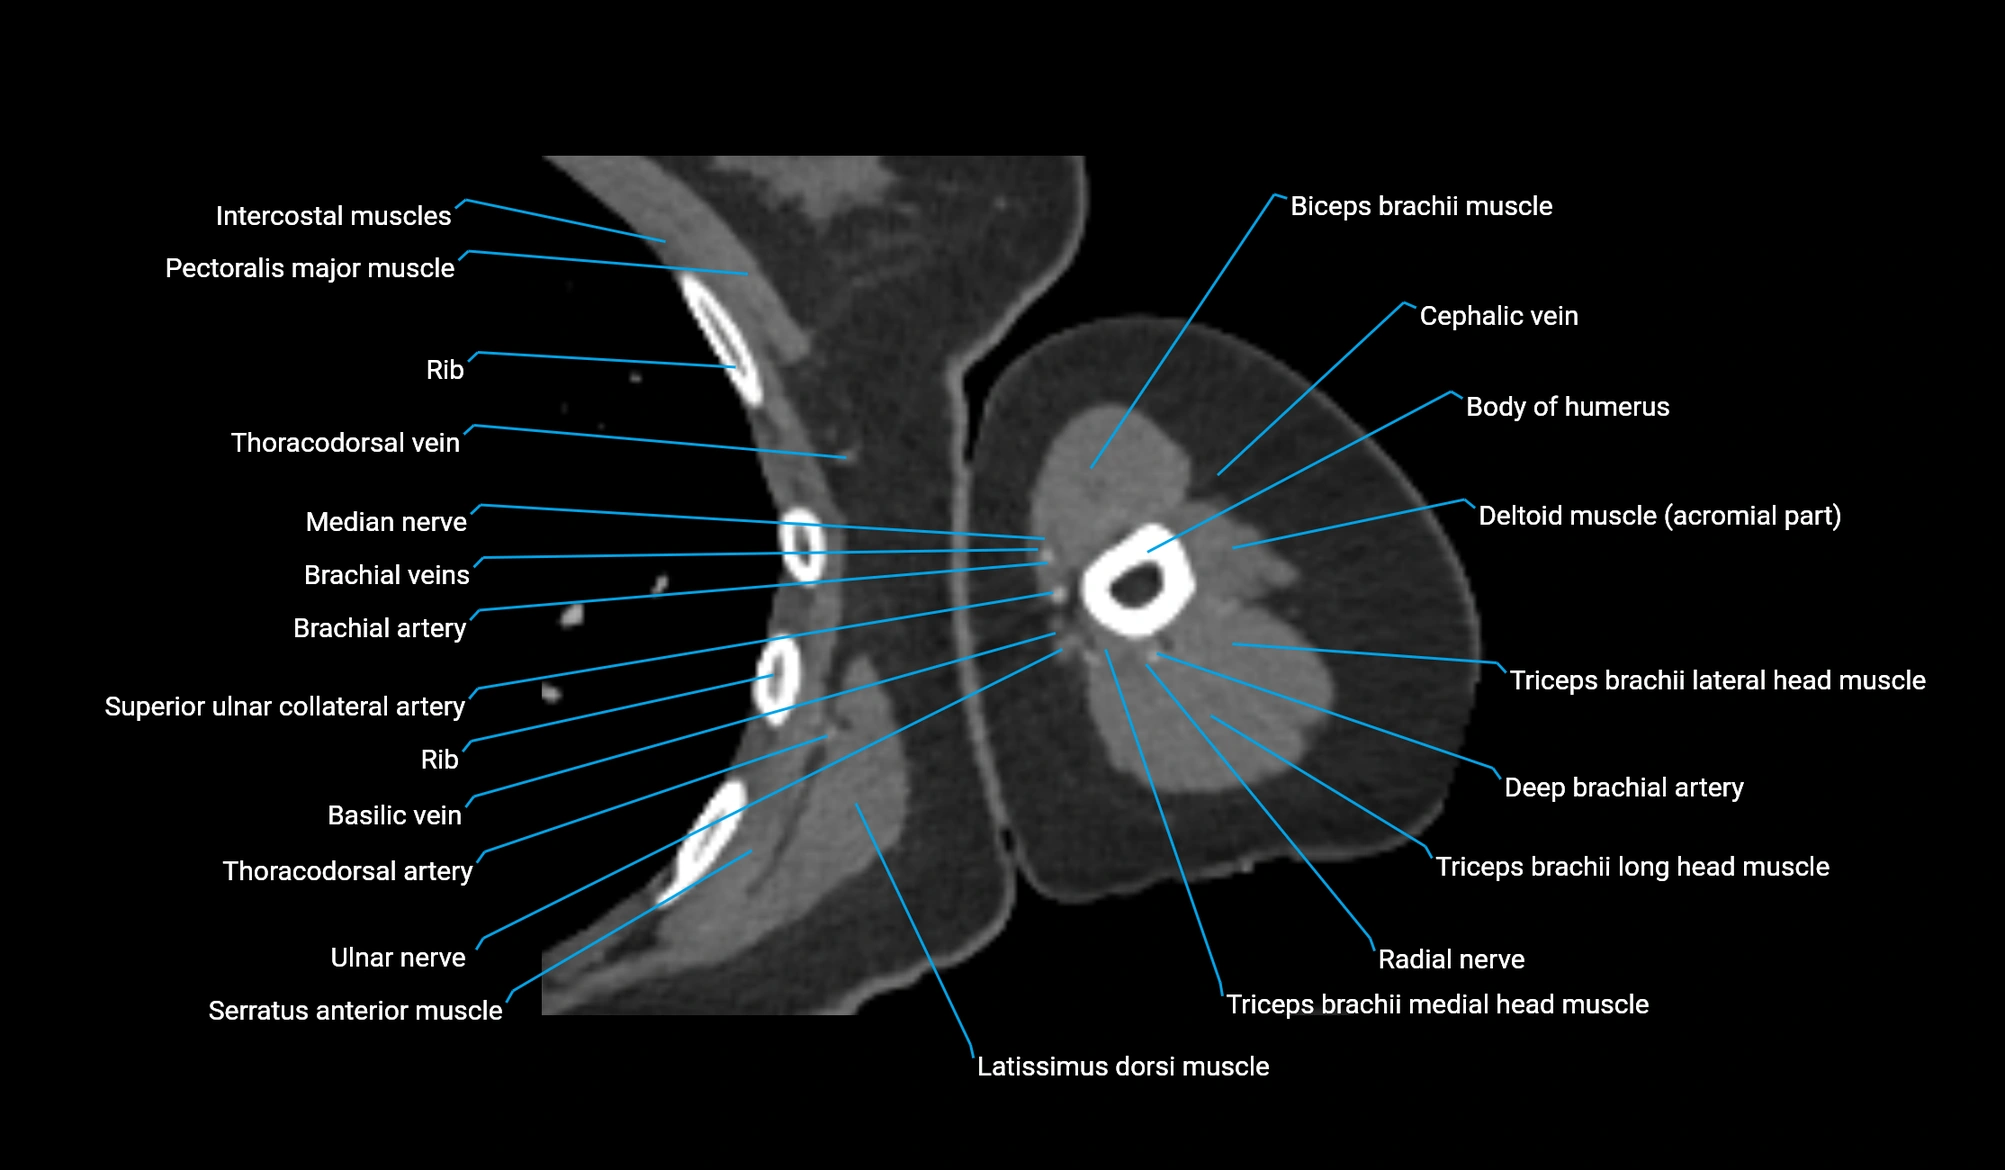

- Body of humerus

- Brachial artery

- Cephalic vein

- Deep brachial artery

- Lateral head of triceps brachii muscle

- Long head of triceps brachii muscle

- Medial head of triceps brachii muscle

- Median nerve

- Radial nerve

- Superior ulnar collateral artery

- Thoracodorsal artery

- Ulnar nerve